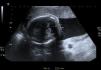

Ecografía a las 31 + 3 semanas: acorde con 25 + 4 semanas de gestación, se objetiva una cisterna magna de 11mm, con separación del vérmix cerebeloso, microcefalia (fig. 1) y malformación de los dedos de la mano, con falanges incurvadas y dedos rígidos (camptodactilia) (fig. 2); se ofrece la posibilidad de realización de amniocentesis, que acepta, y se cita para resultados en 2 semanas.

Ecografía a las 32 + 5 semanas: acorde con 27 + 2 semanas, PFE: 1.097 g, pelvis renales de 8 y 13mm, fosa posterior de 11,5mm. Se realizan Doppler AU y ACM, que resultan ser normales. Se ofrece la posibilidad de interrupción de gestación por sospecha de síndrome polimalformativo, pero los padres deciden continuar con el embarazo.

Ecografía a las 34 + 4 semanas: acorde con 28 + 2 semanas, PFE: 1.245 g. Manos malformadas y pies toscos«en mecedora» (fig. 3). Malformación de Dandy-Walker con cisterna magna de 22mm, sin cambios. Doppler AU y ACM, normales.

Ecografía a las 37 semanas: acorde a 29 + 2 semanas de gestación, PFE: 1.413 g. Doppler AU y ACM normal, crecimiento intrauterino retardado precoz, Dandy-Walker, iv ventrículo de 18mm, cisterna magna de 24mm, microcefalia, ambas manos malformadas, con falanges acortadas y carpo deforme, aspecto simiesco. Se remite a paritorio para RCTG.